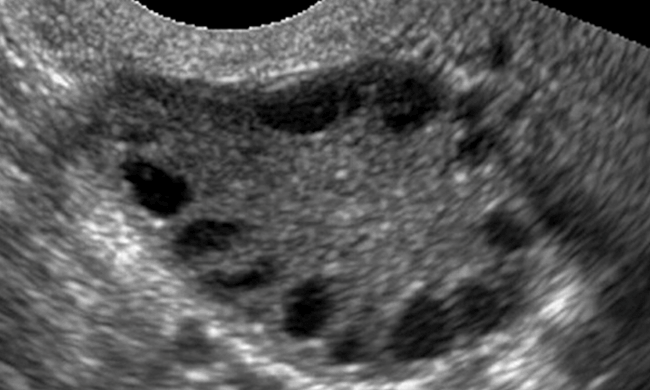

如果没有体重问题、月经异常或不孕症,“多囊卵巢”可能是一种正常现象。如果存在这些问题,那么多囊卵巢可能预示着存在一种叫做多囊卵巢综合症的代谢疾病。(多囊卵巢综合症)